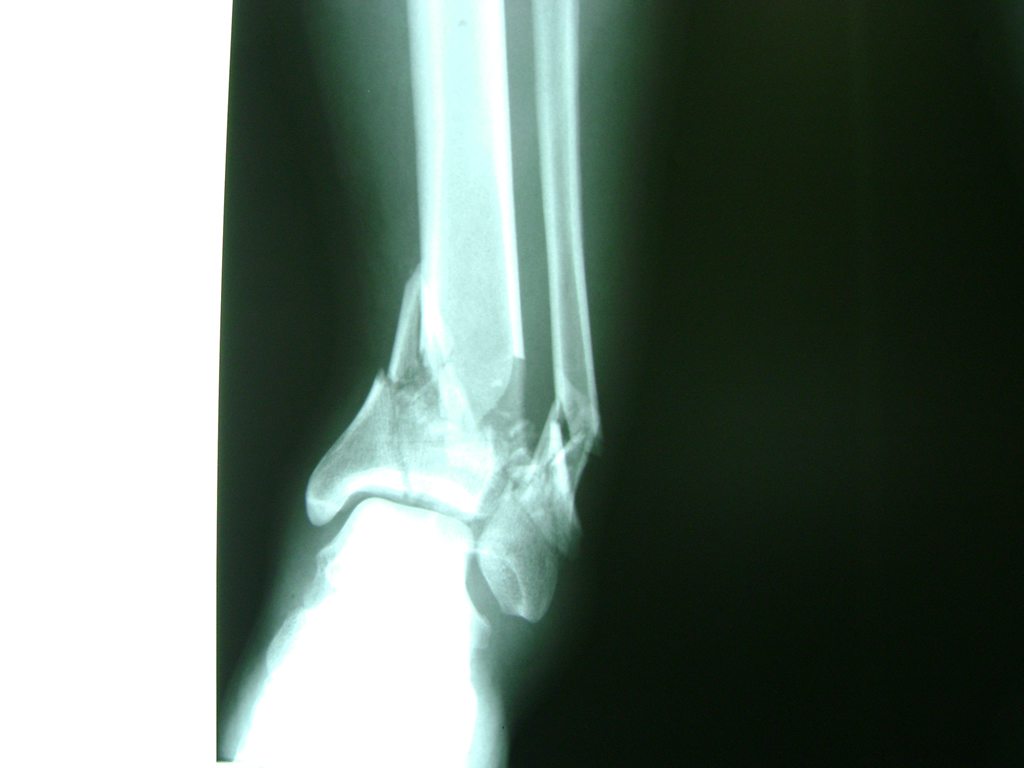

Una fractura de tobillo es la rotura de uno o más de los huesos del tobillo. Estas fracturas pueden ser:

- Los extremos de los huesos están desalineados entre sí (desplazados).

- La fractura se extiende hasta la articulación del tobillo (fractura intra-articular).